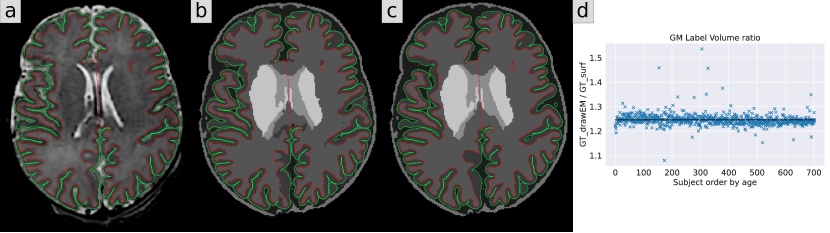

We illustrate these two types of ground truth segmentation maps in Fig. 1, with a plot showing the GM volume ratio (GT_drawEM/GT_surf) by subject, ordered by age. While the differences might look subtle visually on a single slice, we measured an average 25% increase of GM volume in the GT_drawEM compared to GT_surf. This ratio is not influenced by the age of the baby. In this study, we use these two different, but both anatomically plausible, pseudo-ground truths to assess the influence of the definition of the segmentation map on the predictions of the models.

Refer to caption

Figure 1: Illustration of the two different ground truths used in our study. We overlay in red and green the internal and external GM surfaces resp. a) original T2w; b) label map from GT_drawEM; c) label map from GT_surf. d) Volume of GM from GT_drawEM divided by the volume of GM from GT_surf for each subject, ordered by age. The black line represents the mean value of 1.25, illustrating a 25% increase of GM volume in GT_drawEM compared to GT_surf.